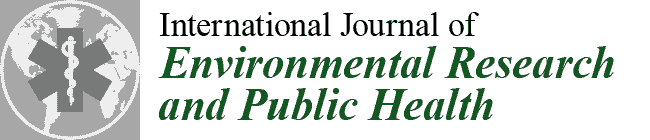

2.1. Case 1